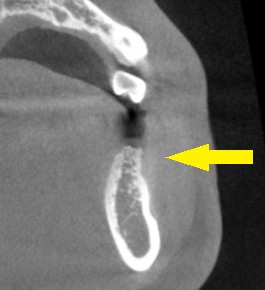

CTを撮影してみると、確かに、骨幅が狭く、十分な骨の厚みを確保してインプラントを長期に安定した状態にしたいとなると、骨を増やす手術が必要でした。

下の写真に手術前後のCTを示します。